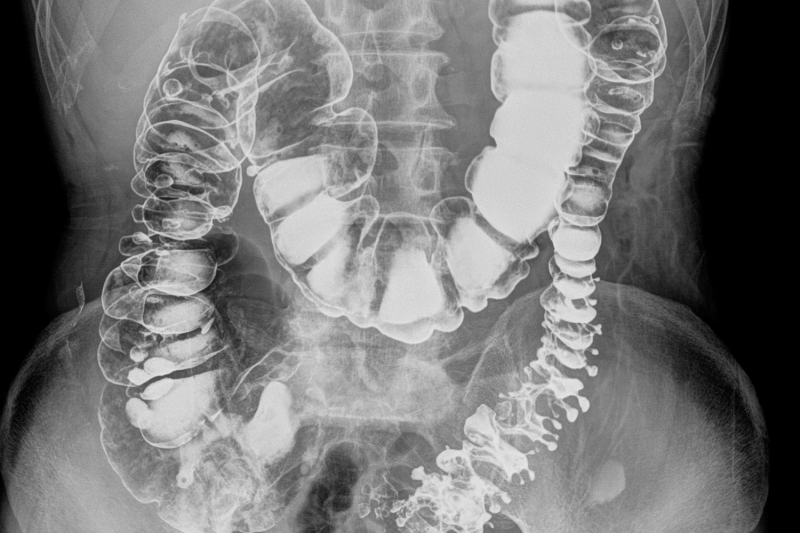

As part of one of Australia's leading health services, Alfred Health Radiology is one of the most advanced radiology departments in the country. We are accredited to DIAS (Diagnostic Imaging Accreditation Scheme) in all modalities excluding DEXA and research.